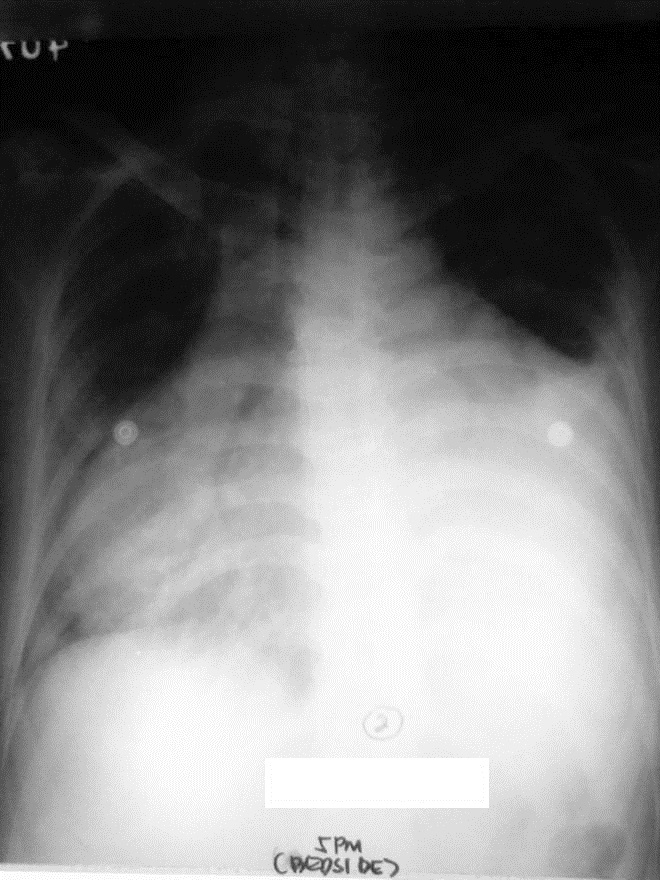

Nineteen days later, the patient noted recurrence of exertional dyspnea, bipedal edema and three-pillow orthopnea. No chest pain or fever was observed. Upon readmission, she was tachycardic with distended neck veins, muffled heart sounds and Grade 2 bipedal edema. Deep tendon reflexes were normal with no tremors. Chest radiograph now revealed multichambered cardiomegaly (Figure 2.)

Click here to download Figure 2Figure 2. Chest radiograph on readmission showing multi-chambered cardiomegaly and characteristic water-bottle sign indicative of massive pericardial effusion.